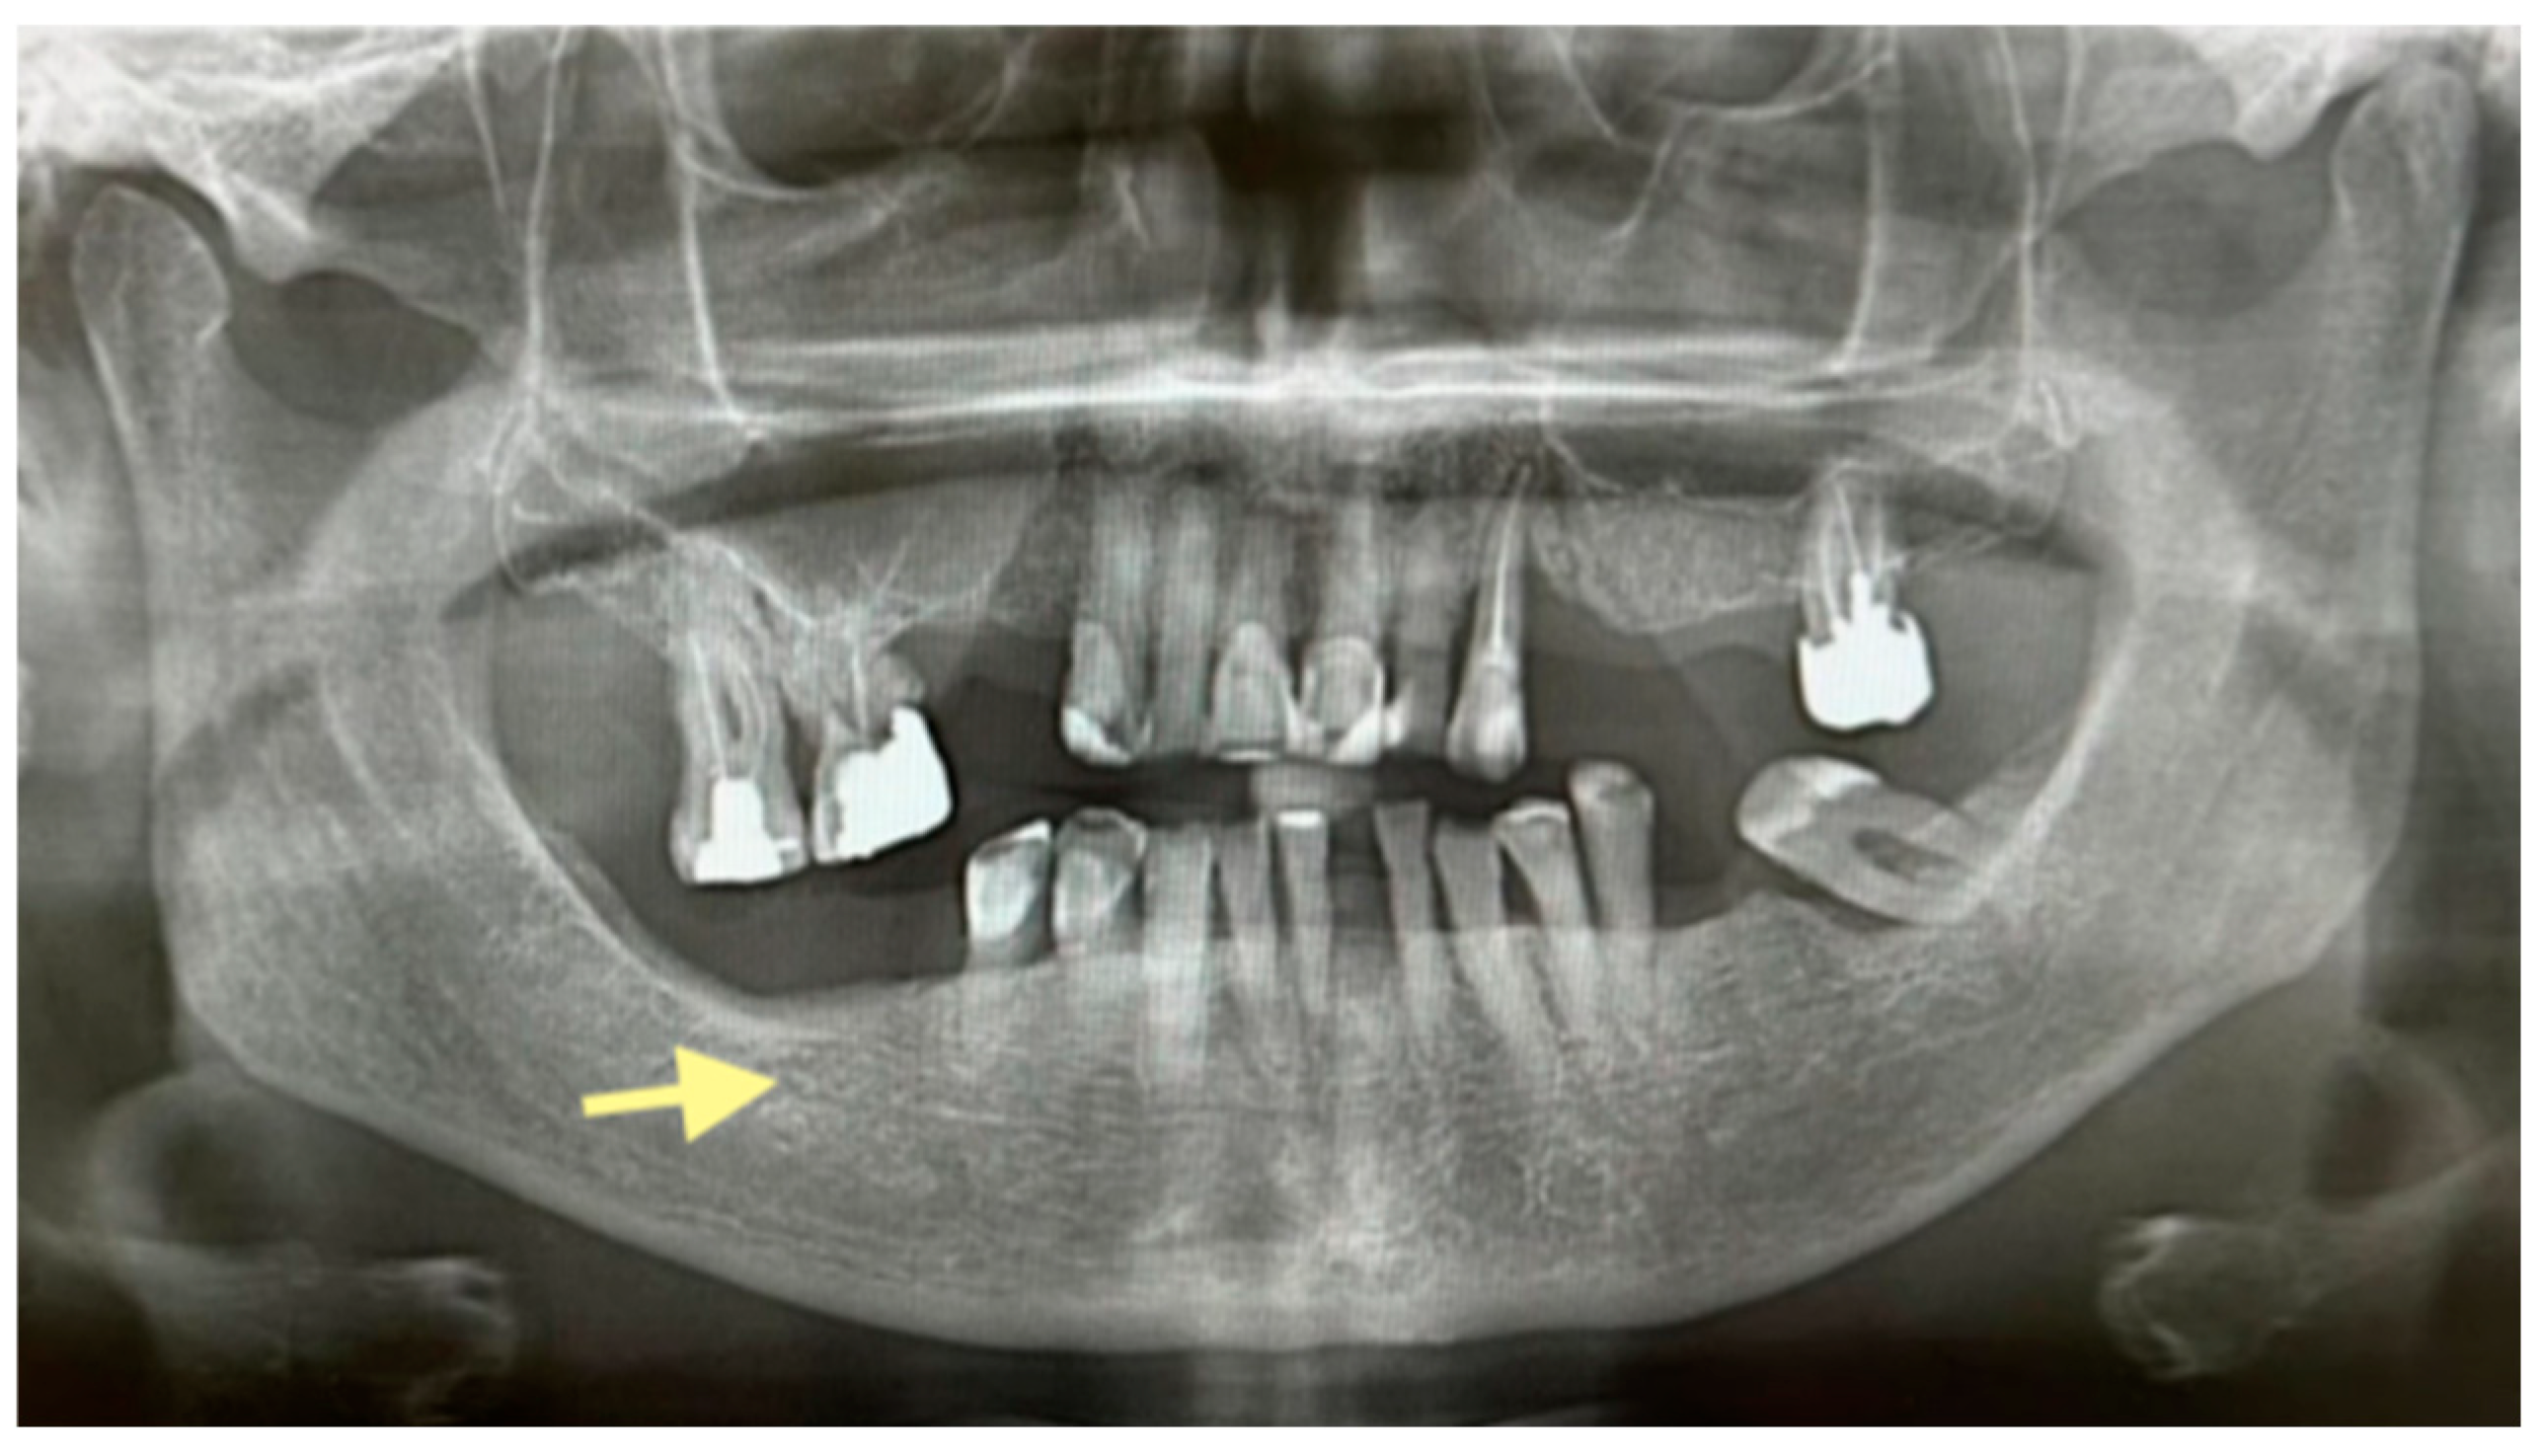

Figure 8.

CT of the head and facial bones (16 December 2024).